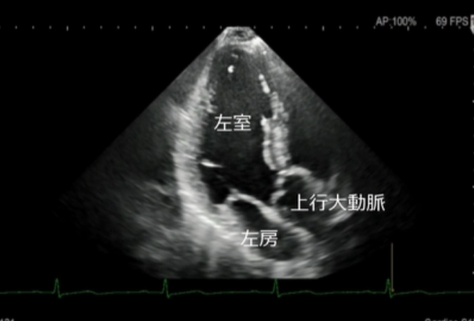

心エコー検査は、超音波を用いて心臓の形や動き、血流の流れを詳しく観察する検査です。

放射線を使用しないため、身体への負担が少なく、安全に繰り返し行うことができます。

エコー(心臓超音波)検査

- このようなことが分かります

弁膜症の評価

心臓の弁(大動脈弁・僧帽弁など)の開き具合や逆流の有無を確認します。

弁の狭窄や逆流の程度を評価し、治療方針の判断に役立てます。 - 心筋の働き(ポンプ機能)の評価

心臓がどのくらいしっかり血液を送り出せているか(収縮機能)を確認します。

心筋梗塞後の機能低下や、拡張型心筋症などの診断にも重要です。 - 心不全の原因検索

息切れやむくみなどの心不全が疑われる場合、その原因が弁膜症によるものか、心筋の

弱りによるものかを詳しく調べます。 - その他

心肥大の有無・心臓内血栓の確認・先天性心疾患の評価・肺高血圧症の推定 など - 検査について

検査時間はおおよそ20~30分程度です。

ベットに横になっていただき、胸にゼリーを塗ってプローブ(探触子)を当て観察します。痛みはありません。

当院では、循環器疾患の早期発見と適切な治療につなげるため、症状がある方は、もちろん、健診等で指摘された方にも心エコー検査を行っております。

お気軽にご相談ください。

超音波診断装置

当院の超音波診断装置(エコー装置)は、高画質で多彩なプローブバラエティと臨床アプリケーションにより、腹部・表在・循環器などの幅広い分野での検査が行えます。当製品はPrecision Imagingを搭載し、超音波画像を形成する信号を処理することにより、組織信号を強調し、生体内組織の境界などの構造視認性を高め、腫瘍部分などがより描出しやすくなっております。